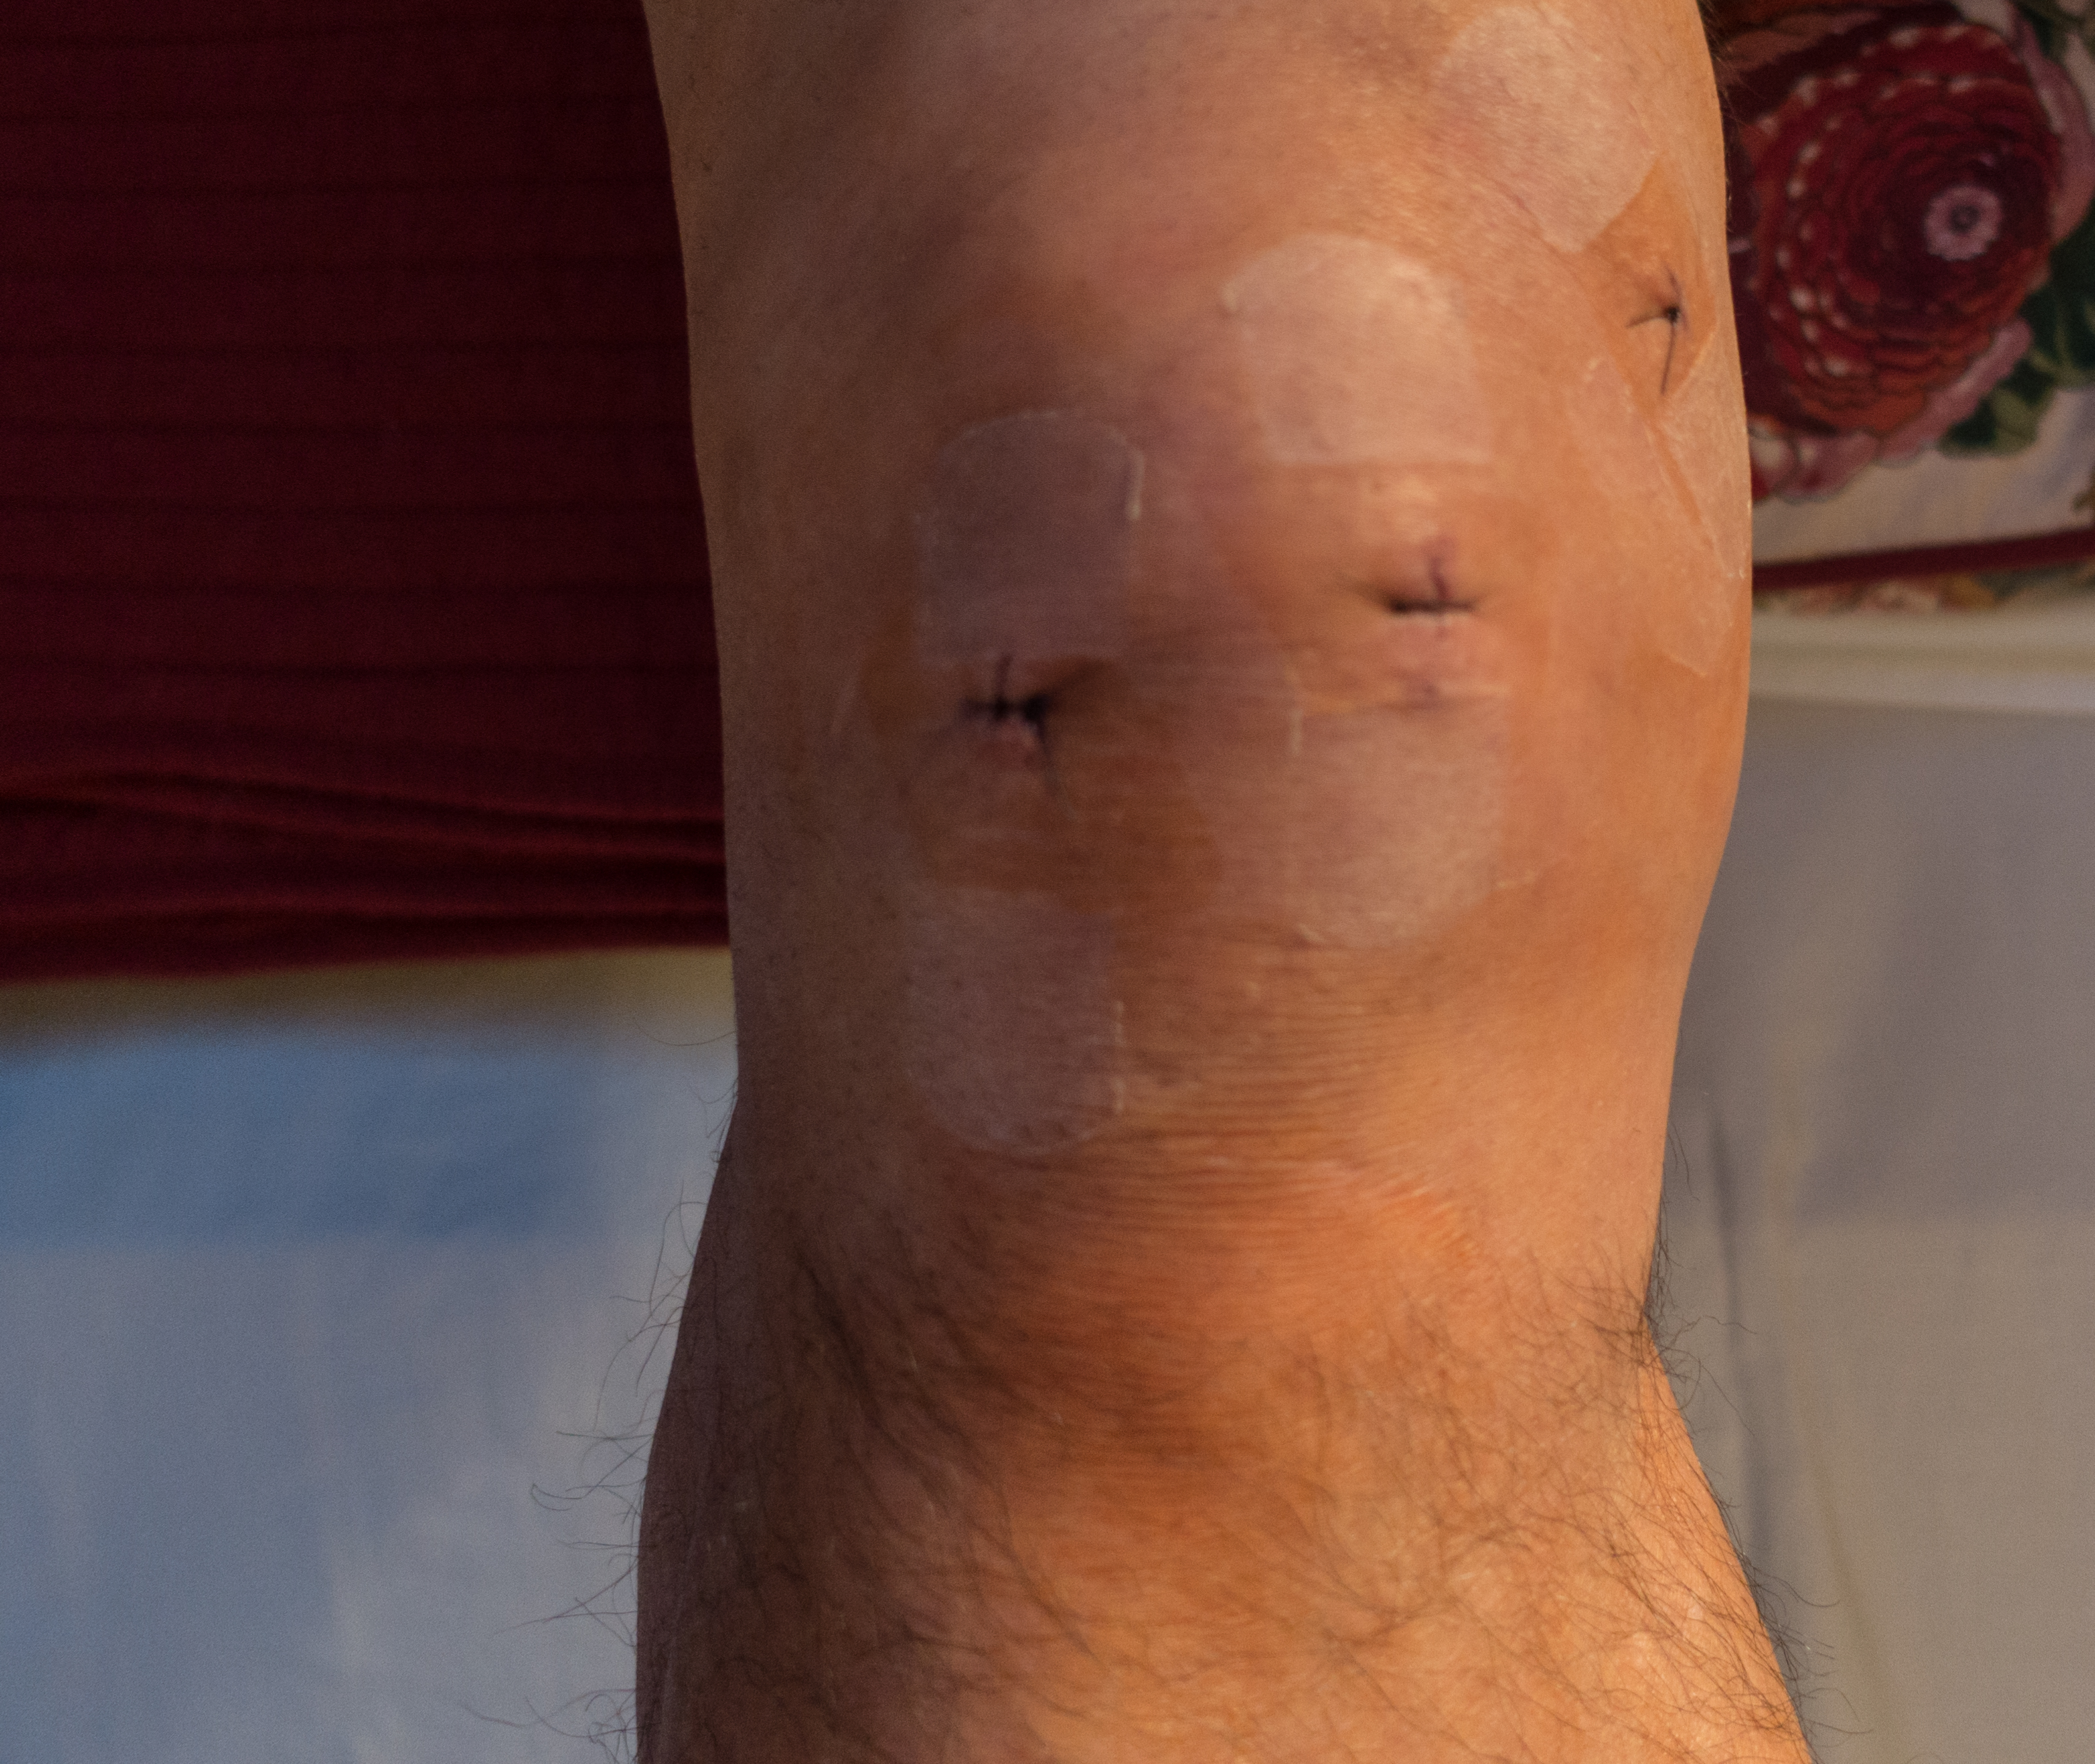

…but feels great. Forty-eight hours after my surgery my knee feels fine. It’s stiff and puffy but I have zero pain and can motor around the house just fine. I hope the next six weeks go as well at the first two days.

12-13-14: Good Day for Surgery

I see on the news that lots of couples are getting married today; supposedly there’s some luck attached to the consecutive numbers in today’s date. Me, I’m doing arthroscopic meniscectomy. After trying rest, cortisone injections, and tons of workouts we decided to have my right knee scoped. A good outcome has me back on the golf course by mid February. I’m certainly not missing many good golf days right now.